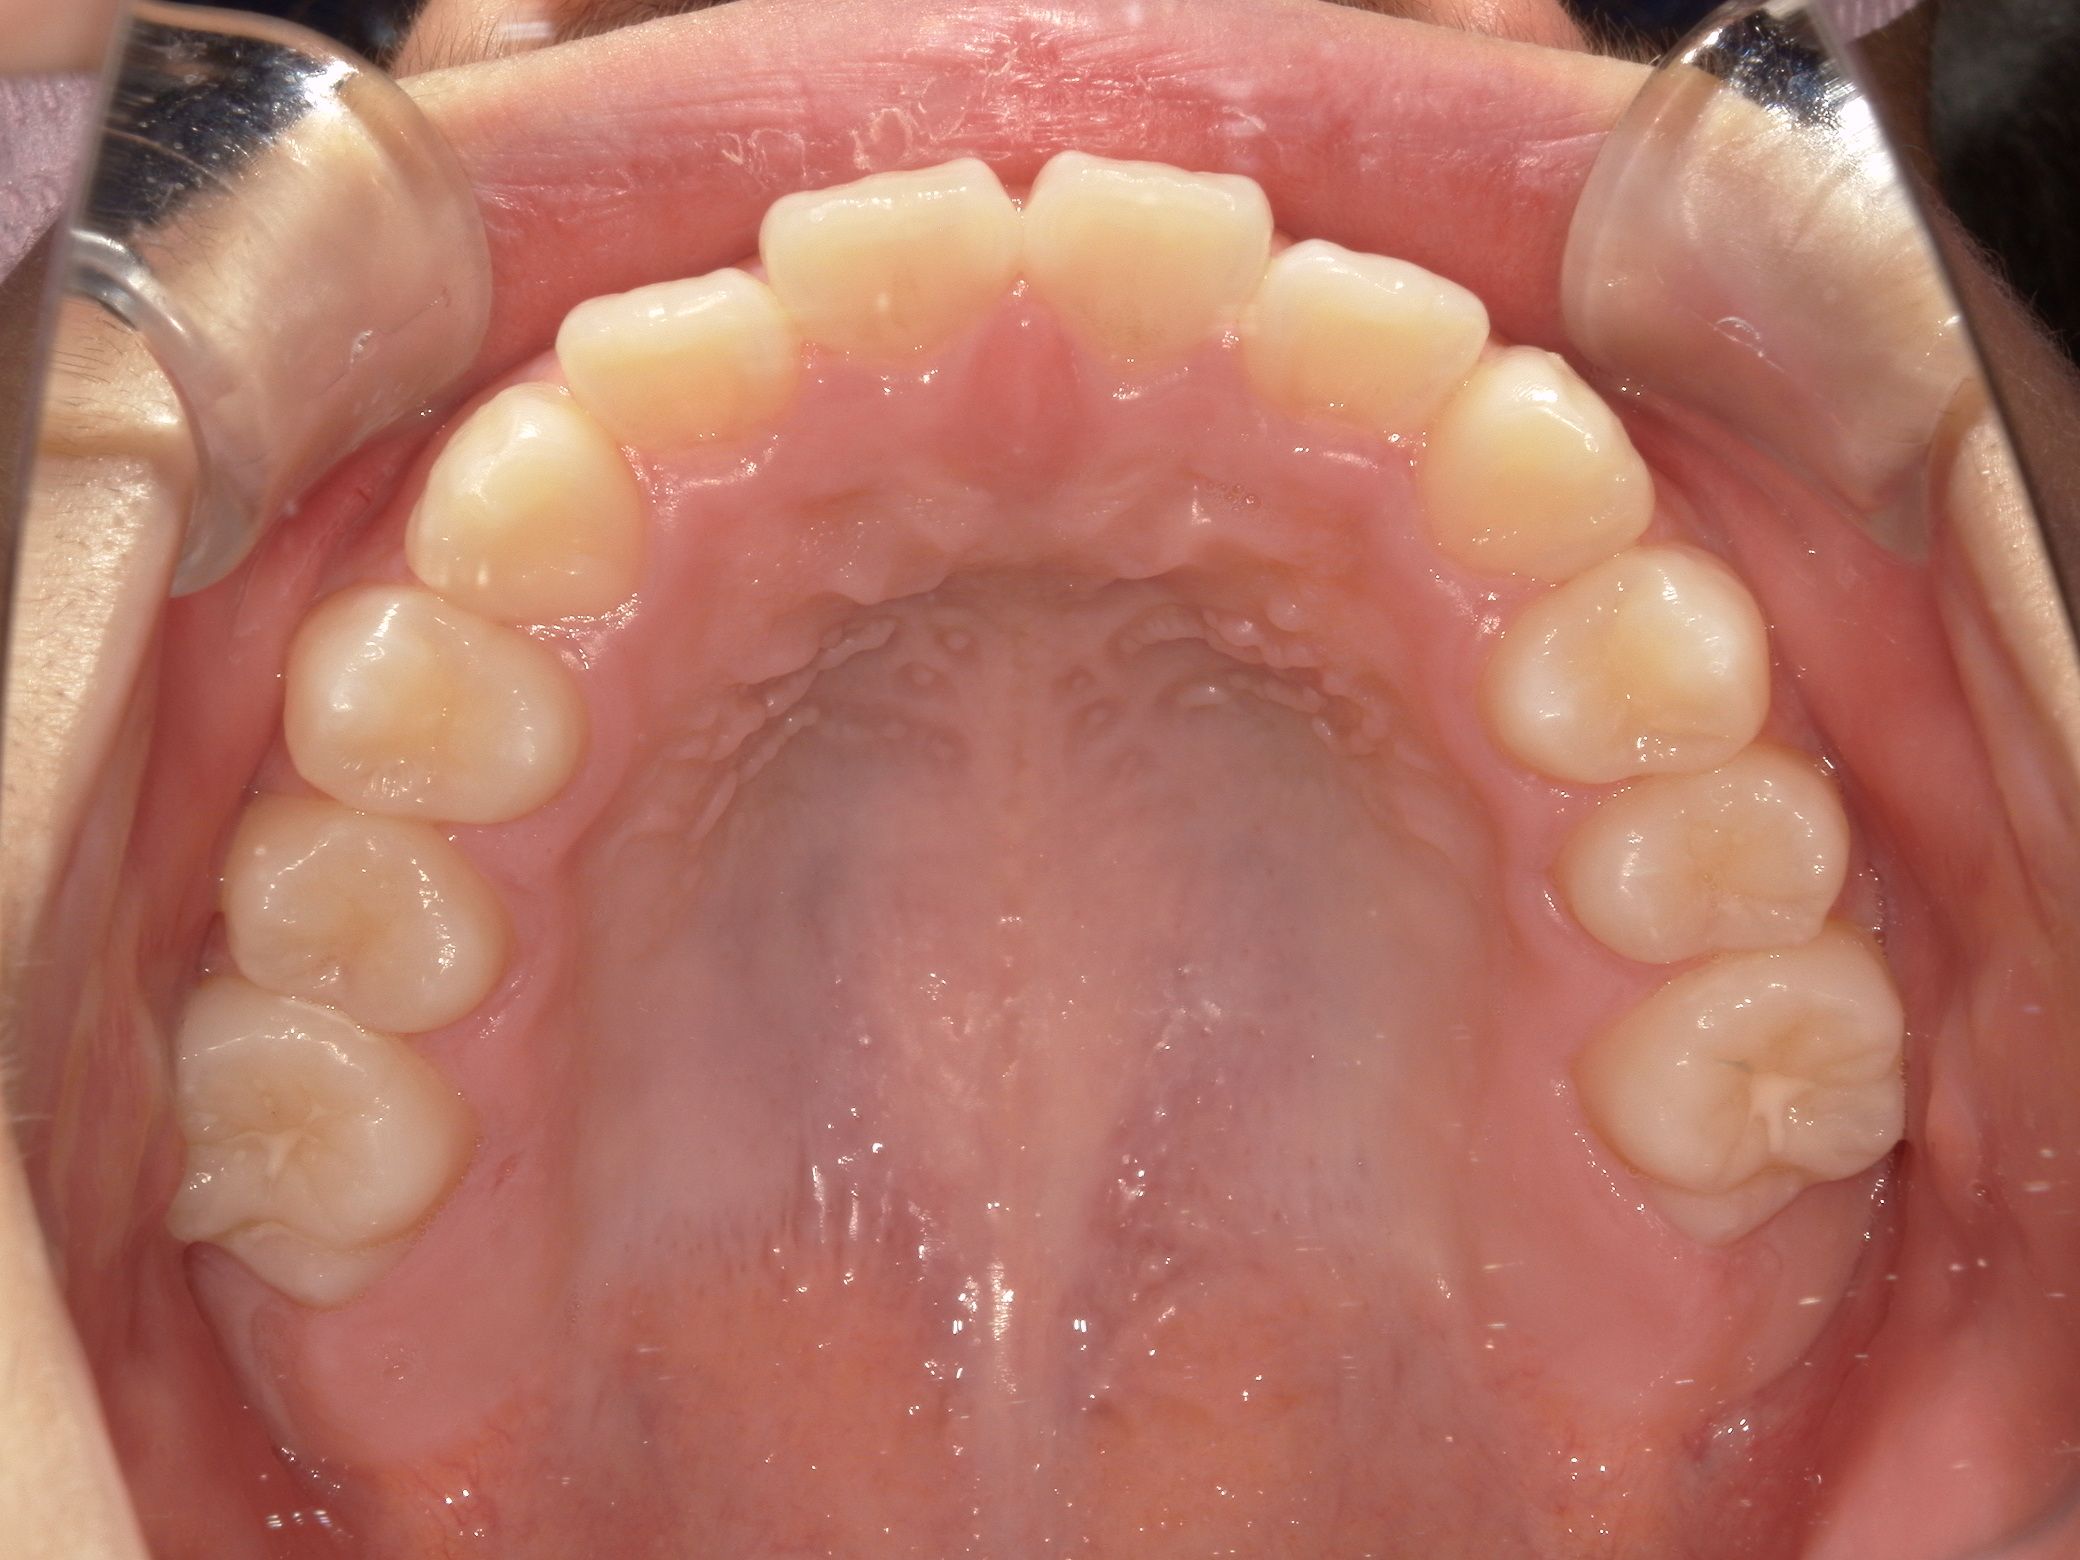

治療後After

ガタつきもなく、きれいなアーチになりました